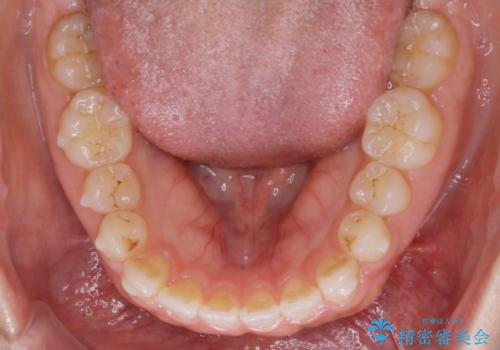

噛み合わせの治療

初診時の写真では一見噛み合わせには問題がないように見えても、実際に精密な検査を行うと改善すべき点が見つかる場合も多くあります。

当院では、矯正治療は見た目の改善が主目的ではなく機能面を改善し自然に長持ちする口腔内環境を整えることに重きを置く必要があると考えます。

しかしながら、こちらの理想だけを押し付けるだけが良い治療とは言えないので、患者様と治療のゴールの設定をよく話し合ったうえで方針を決定していくことが最も重要です。